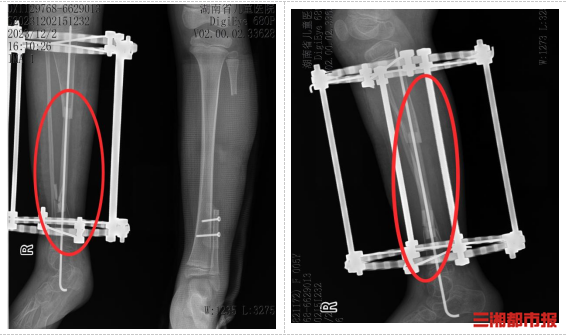

经过两年定期复查,小小移植的腓骨已在新的位置“安家落户”,与胫骨牢固愈合,直径明显增粗,具备了良好的承重能力。他的右下肢长度得到维持,功能恢复良好,生活质量得到了显著改善。